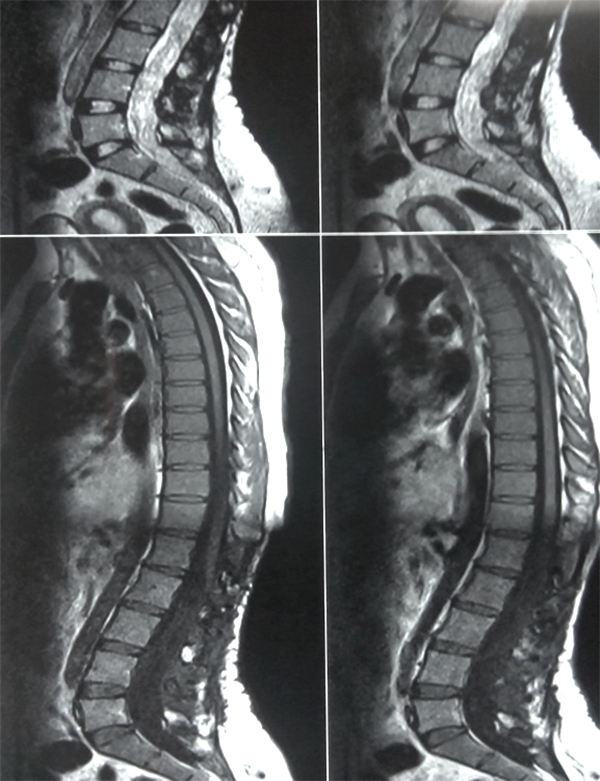

Se registraron dos reoperaciones ( casos 3 y 5 ). En el Caso 5 el paciente experimentó un empiema en el lecho quirúrgico y requirió retiro de la laminoplastía, lavado del foco infeccioso y tratamiento antibiótico por tres semanas, este paciente con Grado 3 en la escala de McCormick se mantuvo con Grado V de la misma escala de manera irreversible luego de un año de la cirugía. El caso 3 se trató de un tumor del cono medular diagnosticado inicialmente como Ependimoma Mixopapilar de la Cola de Caballo (Grado I OMS) en el que observó un residuo sobre la cara anterior medular en una IRM de control (Figuras 1 y 2). La reexploración evidenció la ubicación intramedular de la lesión y la revisión anatomopatológica definitiva concluyó que se trataba de un Ependimoma (Grado II OMS).

Figura 1: Caso 3. Ependimoma Dorsolumbar. Residuo cara anterior